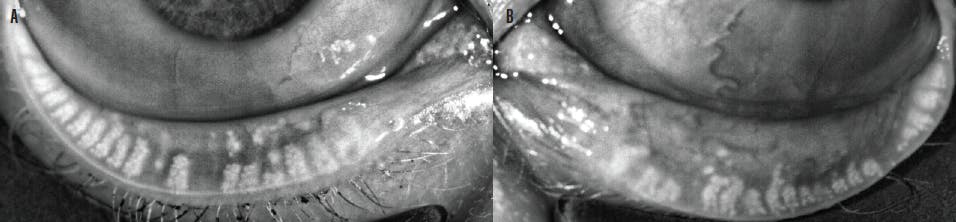

Acne rosacea is one of the most common skin conditions associated with OSD. Some studies have found that 90% of rosacea patients have OSD, and at least half are likely to have concurrent blepharitis.23,24 Thickened meibum oil secretions result from the inflammatory T-cells delivered by multiple irregular telangiectatic blood vessels.23,24 The red flush seen near the surface of the skin of the nose and cheeks is a true red flag to look for concurrent telangiectasia of the lid margin (Figure 4).

Figure 4. Telangiectasia in ocular (A) and facial (B) rosacea.

Secondary demodicosis is common, as thickened secretions and sloughed glandular and follicular epithelial cells create the perfect food source for Demodex mites, resulting in overpopulation.25 IPL is a treatment modality that can help to both regress telangiectatic blood vessels and reduce Demodex populations.26-28 IPL treatment of the periocular region and eyelids has resulted in improvement in measurable indices of OSD, including reductions in ocular inflammation (as measured by the inflammatory marker matrix metalloproteinase 9),29 corneal staining,30,31 meibomian gland turbidity,31 and reported symptoms.31-33 Increases in tear breakup time and lipid layer thickness have also been reported.31-33

Although other common ocular rosacea therapies do not directly treat the underlying telangiectasia, they can target concurrent MGD, blepharitis, and inflammation. These other therapies include okra seed oil– and tea tree oil–based lid treatments,34-35 oral tetracycline derivatives,36 topical cyclosporine,36 topical azithromycin,37 and gland expression techniques.38